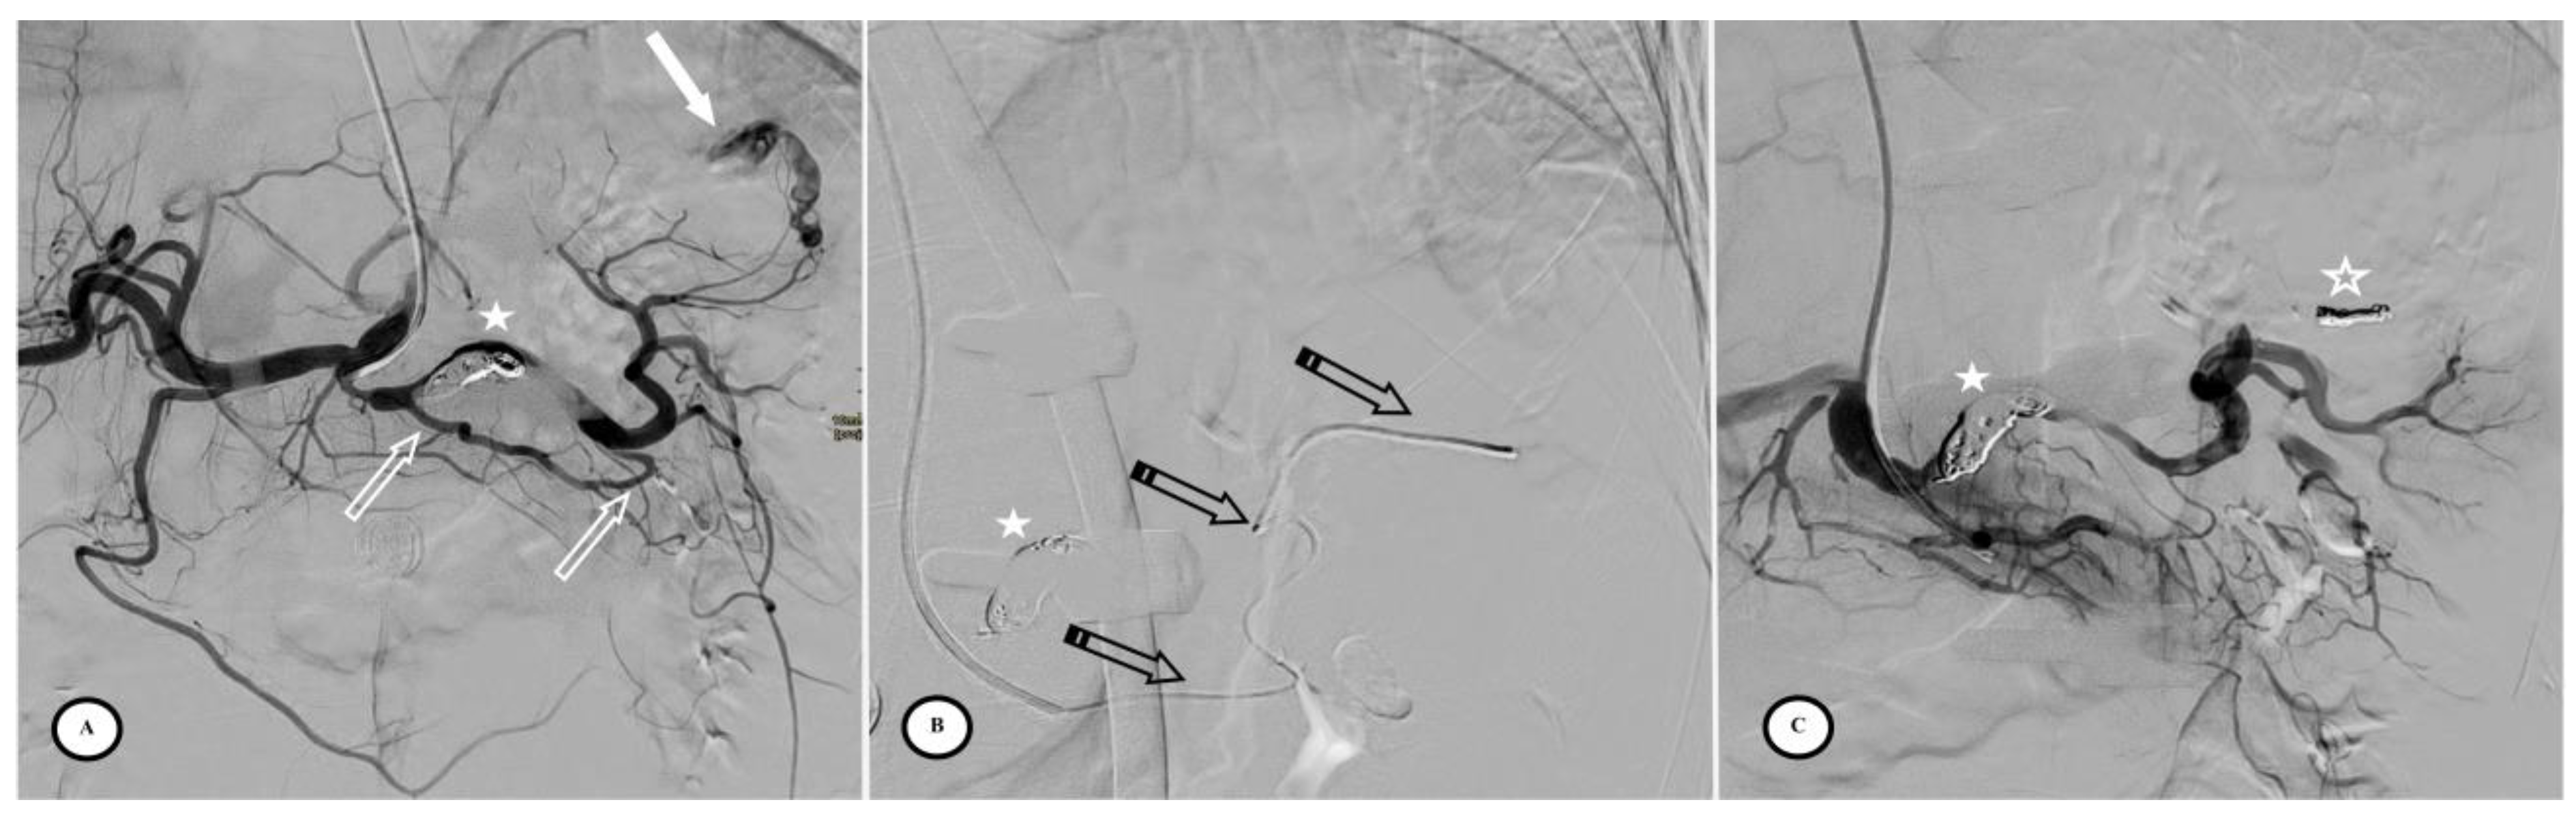

Fifty-three patients had femoral access and only four patients had radial access. Six patients (10.5%) had combined embolization (proximal + distal) due to focal vascular anomalies identified on the DSA but not visible on the initial CT. Embolic agents for distal embolization included gelatin sponge, microcoils, and Onyx®. PPSAE was performed with an Amplatzer™ vascular plug (AVP) in 29 patients (50.9%), a Penumbra occlusion device (POD®) in 18 patients (31.6%), and coils in 10 of the 57 patients (17.5%) (Figure 3).

Figure 3.

Preventive proximal splenic artery embolization materials. (A) Upper pole splenic trauma without focal vascular anomaly (star). (B) Penumbra occlusion device (arrow) deployment through a microcatheter along the left lateral aspect of the spine; note that the patient had osteosynthesis material. (C) Final control shows complete flow stasis in the splenic artery downstream from the embolic material (arrow) and the development of collateral circulation (arrowheads). (D) Another upper pole splenic trauma without focal vascular anomaly (star). (E) Amplatzer vascular plug deployment (blank arrow) directly through the Cobra 2 4F catheter. (F) Final control displays the development of a collateral pathway through the dorsal pancreatic artery and the great pancreatic artery (arrowheads).

Technical success was achieved in 54 of the 57 patients (94.7%) with complete splenic artery stasis and the development of collateral circulation. Inadvertent distal coil migration occurred in four patients in the other coils group (n = 4/10, 40%; p < 0.01). There were no procedural complications with AVP or POD. The mean procedure time for all techniques was 56.5 min (SD = 38.1 min) with no significant difference between groups. The mean quantity of iodine contrast injected was 70.0 mL (SD = 42.0 mL), with less contrast injected in the AVP group (p < 0.01) (Table 3).